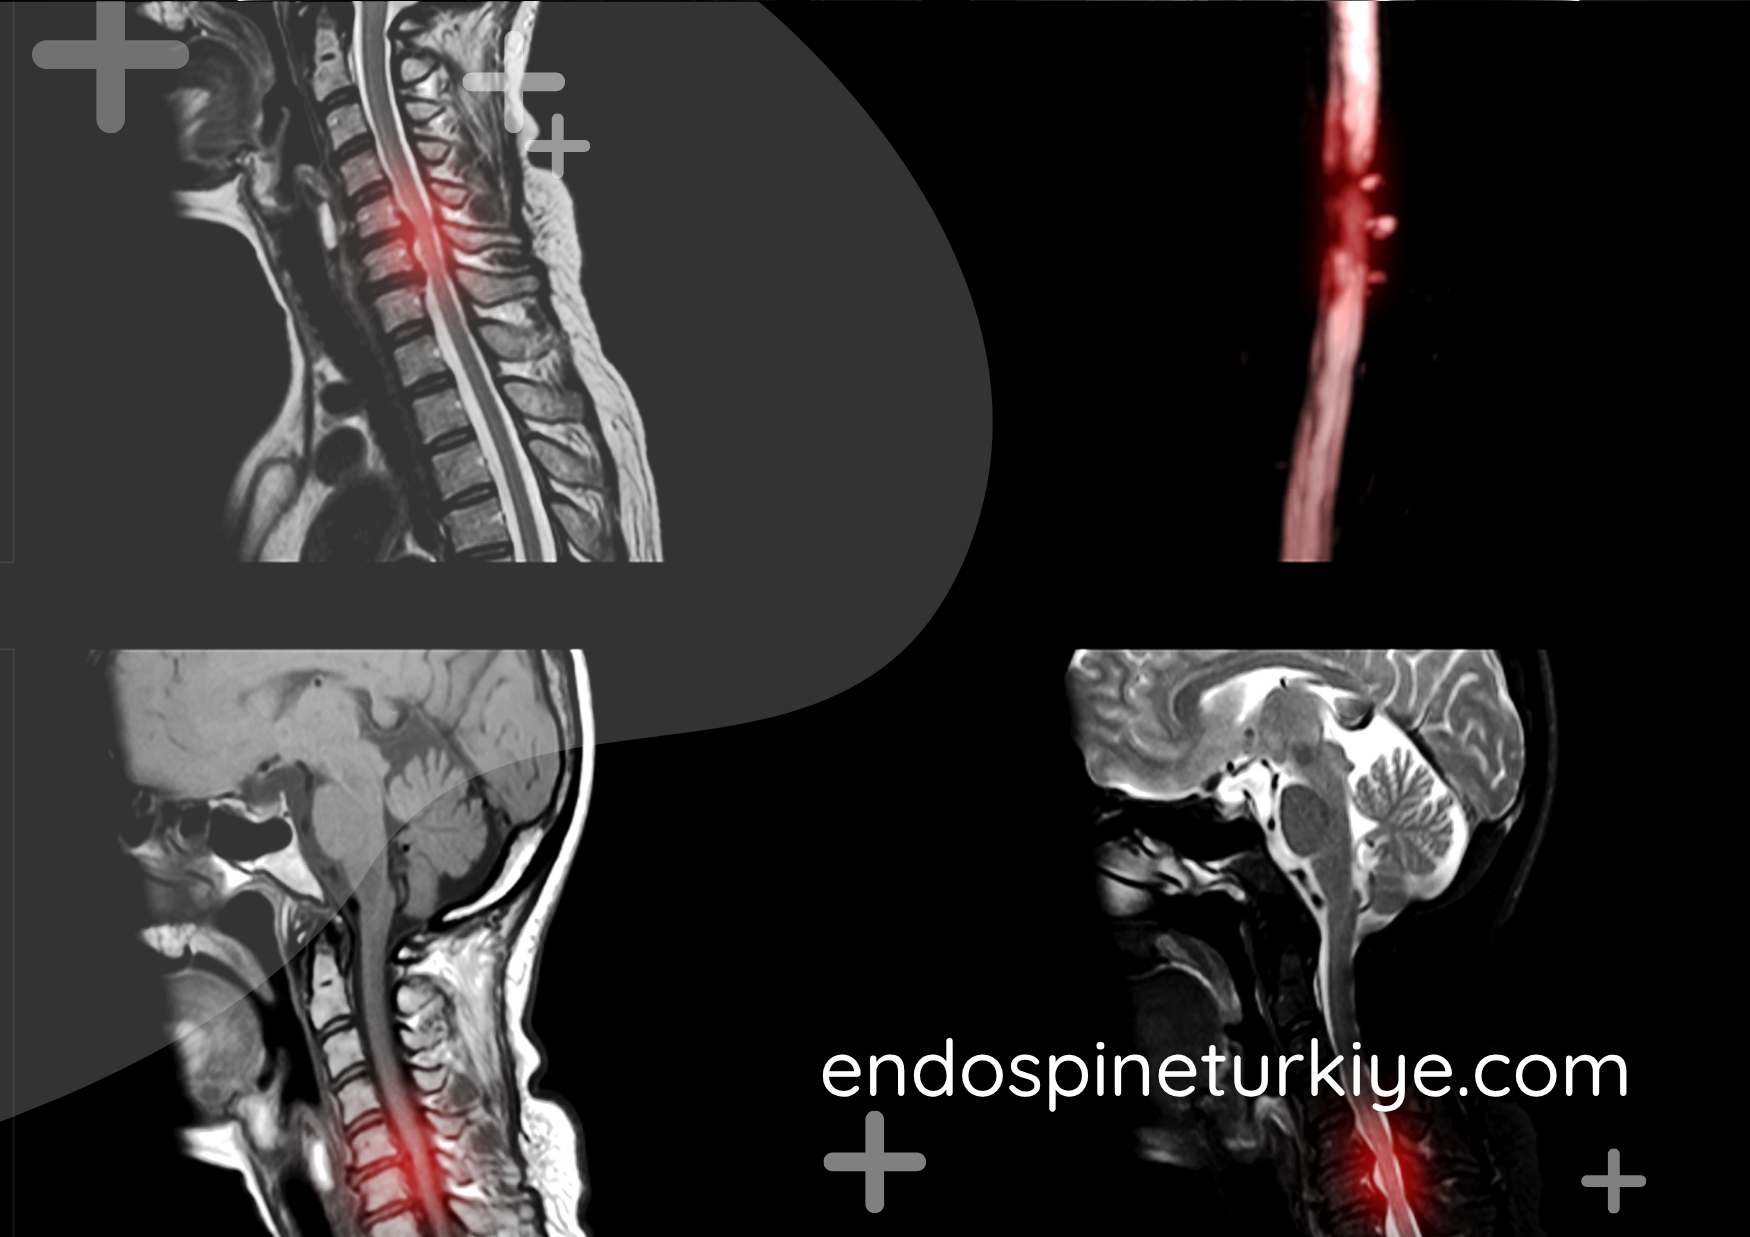

Tam Kapalı Endoskopik Boyun Fıtığı Ameliyatı

Op. Dr. Rifat Saygın Altınağ tarafından PECD (Perkütan Endoskopik Servikal Diskektomi) tekniğiyle uygulanan, diskin ve eklem yapısının muhafaza edildiği tam kapalı boyun fıtığı cerrahisi.

Endoskopik Boyun Fıtığı Ameliyatı Nedir?

PECD (Perkütan Endoskopik Servikal Diskektomi), boyun fıtığının giderilmesinde kullanılan tam kapalı endoskopik cerrahi yöntemidir. Konvansiyonel açık cerrahinin aksine disk yapısı ve eklem bütünlüğü korunur, füzyon (kaynaştırma) işlemi uygulanmaz.

6 haftayı aşan sürede konservatif tedaviden fayda görülmeyen, MR'da belirgin fıtık saptanan, kuvvet kaybı ya da yoğun ağrısı bulunan hastalarda cerrahi endikasyonu oluşur.